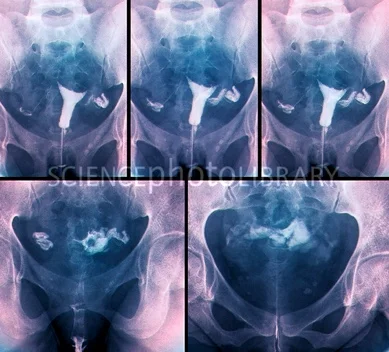

- A-Hysterosalpingography = H.S.G: the main line used for diagnosis by “tubal patency tests”.

The idea: Inject radio-opaque dye in the uterus to pass through the tubes to the peritoneal cavity.

Then the lower abdomen and pelvis are photographed.

Timing of the test: it should be done post-menstrual to minimize chances of interrupting a pregnancy.

Complications:

- Neurogenic shock, hemorrhage due to trauma,

- Infection, perforation of uterus, endometriosis, oil embolism, dye allergy.

Values of HSG:

- Diagnostic for: intrauterine and tubal disorder

- Therapeutic for:

- Removal of mucous plug that may close the tube.

- Removal or absorption of thin adhesions.

- Straightening of kinked tube or relief of uterotubal spasm.